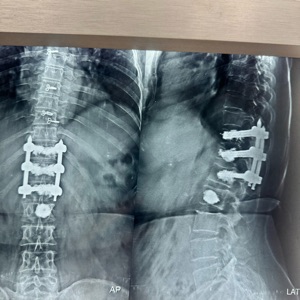

Spinal trauma management involves surgical and non-surgical interventions to stabilize the spine and protect neural elements. Techniques include instrumentation with rods, screws, and plates, spinal fusion, and in some cases, vertebroplasty or kyphoplasty for vertebral compression fractures. The approach depends on injury severity, location, and neurological involvement, aiming to restore spinal alignment and function.